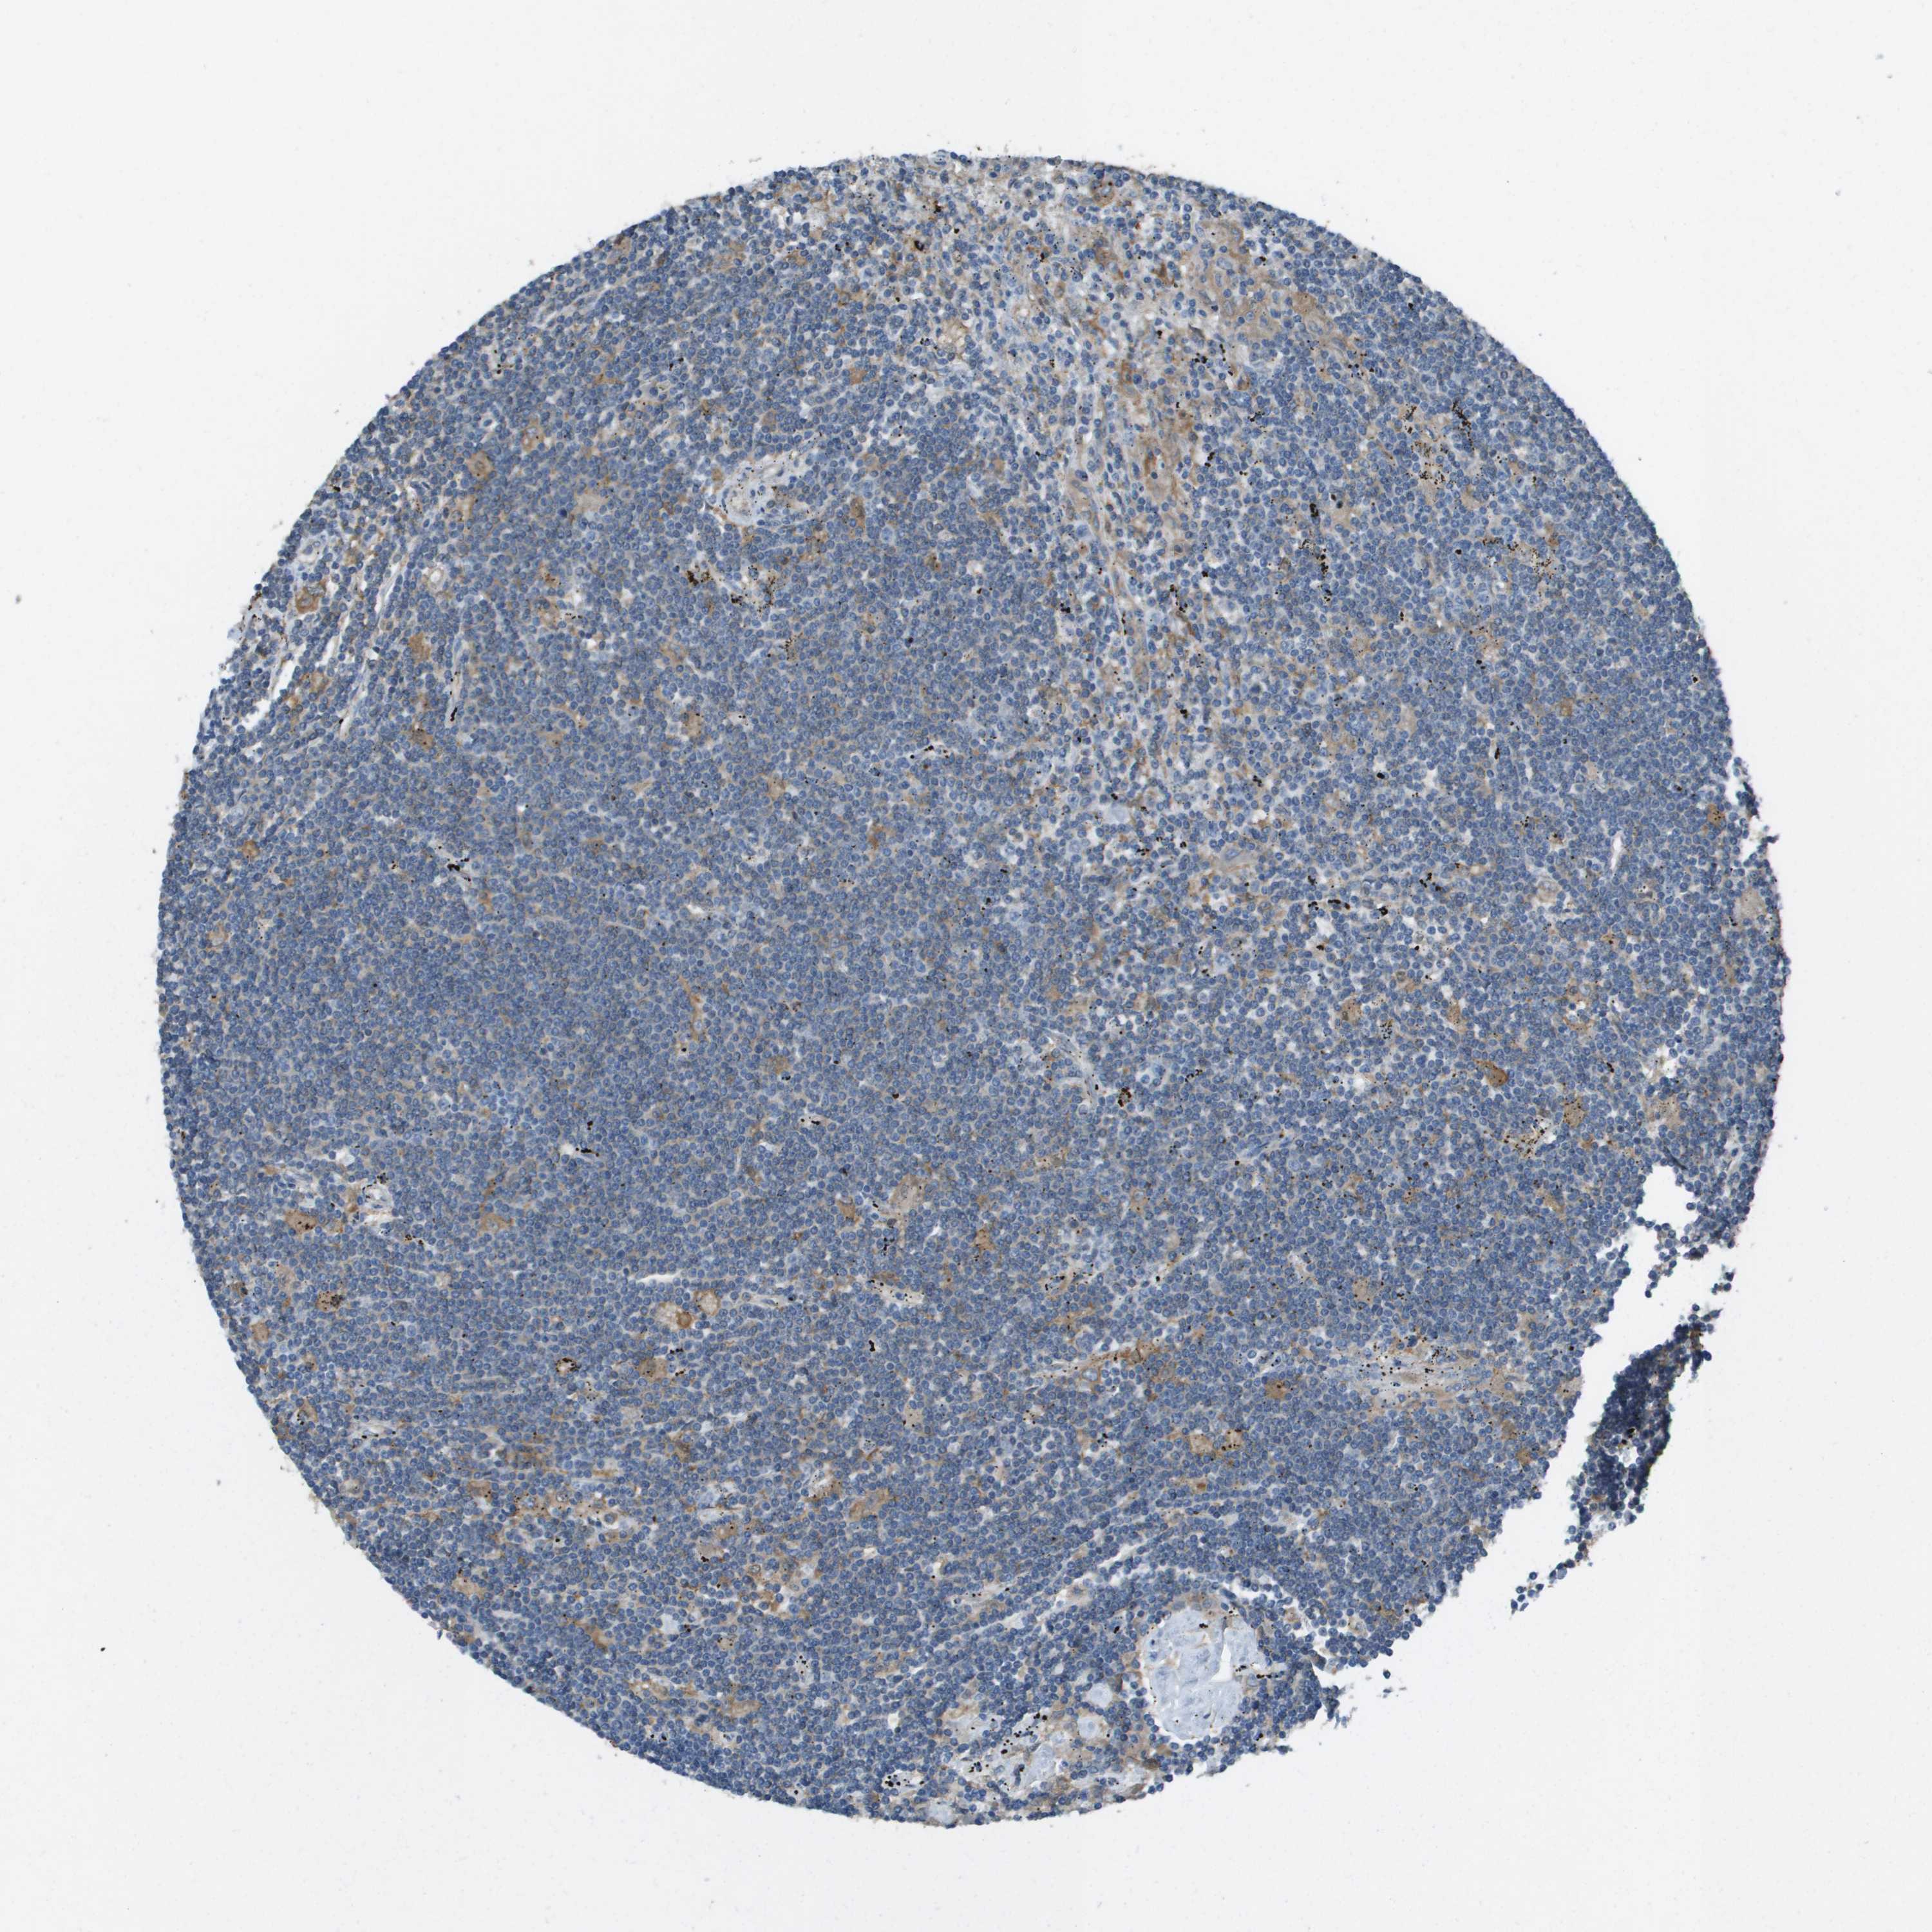

CANCER LYMPHOMA Show tissue menu

LYMPHOMA - Protein expressioni

A mouse-over function shows sample information and annotation data. Click on an image to view it in a full screen mode. Samples can be filtered based on level of antibody staining by selecting one or several of the following categories: high, medium, low and not detected. The assay and annotation is described here.

Antibody stainingi

Antibody staining in the annotated cell types in the current human tissue is reported as not detected, low, medium, or high, based on conventional immunohistochemistry profiling in selected tissues. This score is based on the combination of the staining intensity and fraction of stained cells.

Each image is clickable and will lead to virtual microscopy that enables deeper exploration of all samples and also displays staining intensity scores, fraction scores and subcellular localization as well as patient and tissue information for each sample.

Antibody HPA070456

Antibody CAB017616

Staining

High

Medium

Low

Not detected

Intensity

Strong

Moderate

Weak

Negative

Quantity

>75%

75%-25%

<25%

None

Location

Nuclear

Cytoplasmic/membranous

Cytoplasmic/membranous,nuclear

Malignant lymphoma, non-Hodgkin's type, Low grade

Malignant lymphoma, non-Hodgkin's type, High grade

Hodgkin's disease, NOS